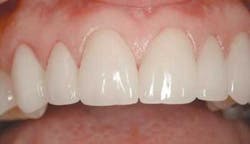

From this information, we are able to ascertain many things. First, after ruling out any periodontal disease and noting a comfortable and asymptomatic TMJ, we can turn our attention to the esthetic concerns. As you can see in figure 2, there are many things that can be improved. Let's go through this very methodically, using principles taught by the experts in the field, and see what we can improve.

With our patient, this evaluation reveals the centrals to be approximately 8.5 mm wide and 9.5 mm long. (Fig. 3) This would make the existing W/L ratio 89 percent. The Golden Proportion evaluation shows that the centrals appear too wide and we see too much of the canines.

Here we want to evaluate the curvature of the incisal edges compared to the lip. These edges should follow the basic curve of the lower lip. It should not be flat or reversed. This ages the smile tremendously. Our patient's incisal edges follow her lip fairly well. (Fig. 2)